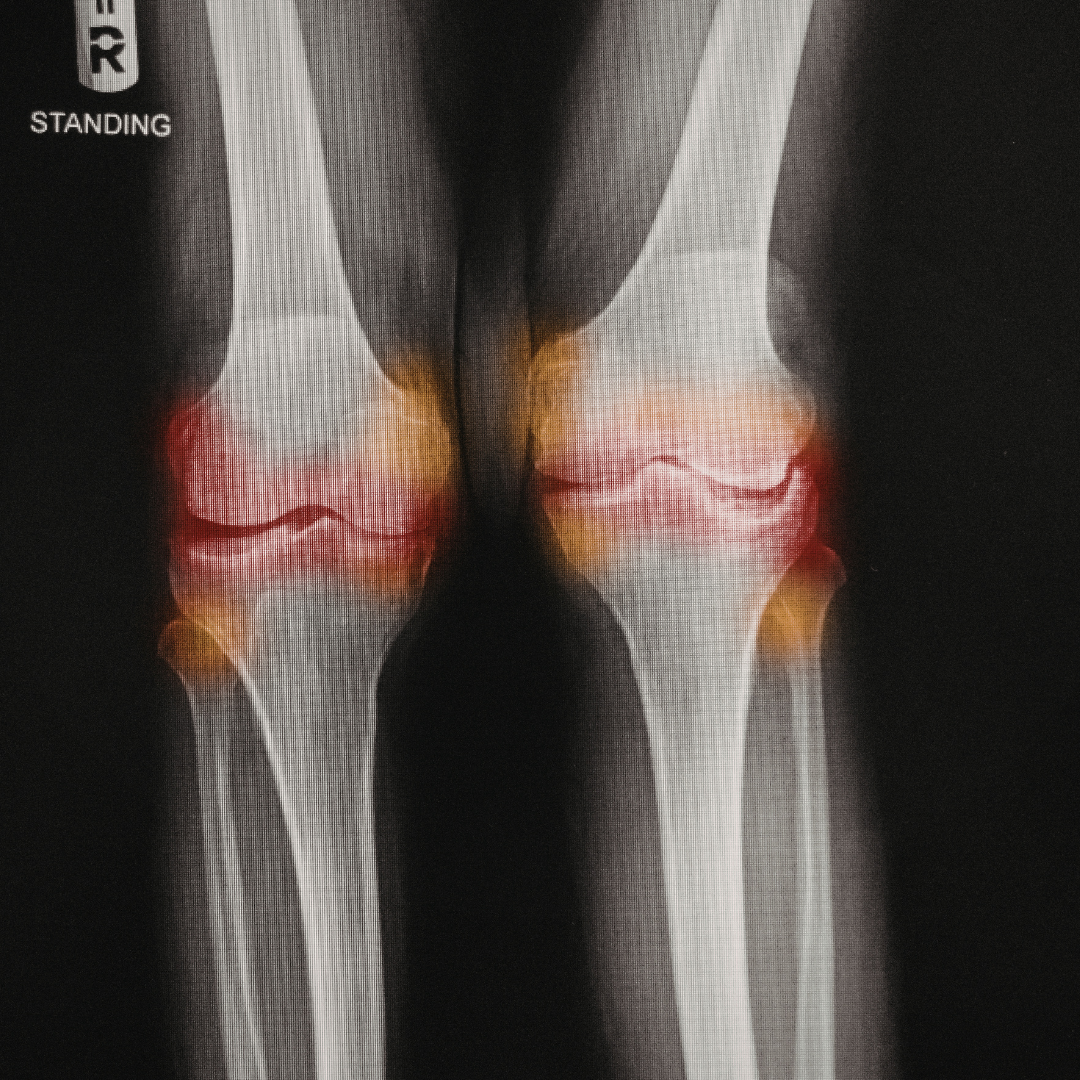

2. Your Joints Start to Ache

Have you felt stiff in the mornings lately? Joint pain is one of the most common complaints of menopause. Without estrogen to reduce inflammation, your joints can become swollen and painful. This can make exercise difficult, which creates a vicious cycle of inactivity and more stiffness.